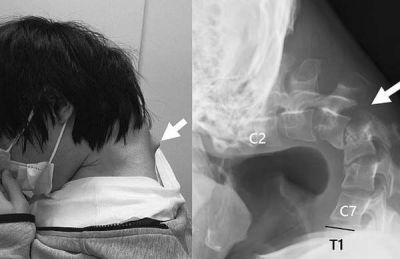

의료진은 "고개를 숙인 채 오랜 시간 스마트폰 게임을 하면서 목의 척추뼈가 탈구(뼈가 제자리를 이탈하는 현상)됐다"며 "환자의 목 뒷부분에 흉터처럼 혹이 튀어나왔는데, 비정상적인 자세 때문에 척추뼈가 극도로 늘어난 결과"라고 말했다.

매일 장시간 스마트폰 게임을 한 결과 목이 꺾이는 ‘머리떨굼 증후군’에 걸린 남성의 엑스레이 사진 [이미지 출처=사이언스 다이렉트 캡처] |

이에 의료진은 우선 목을 고정하는 의료 기기를 이용해 교정을 시도했다. 그러나 남성이 감각 이상을 호소하면서 결국 목뼈에 나사와 금속 막대를 삽입하는 수술을 진행했다.

수술 후 6개월 만에 이 남성은 머리를 수평으로 유지할 수 있게 됐고, 1년 뒤 추적 검사에서 머리떨굼 증후군 증상이 재발하지 않은 것이 확인돼 일상으로 돌아올 수 있었다.